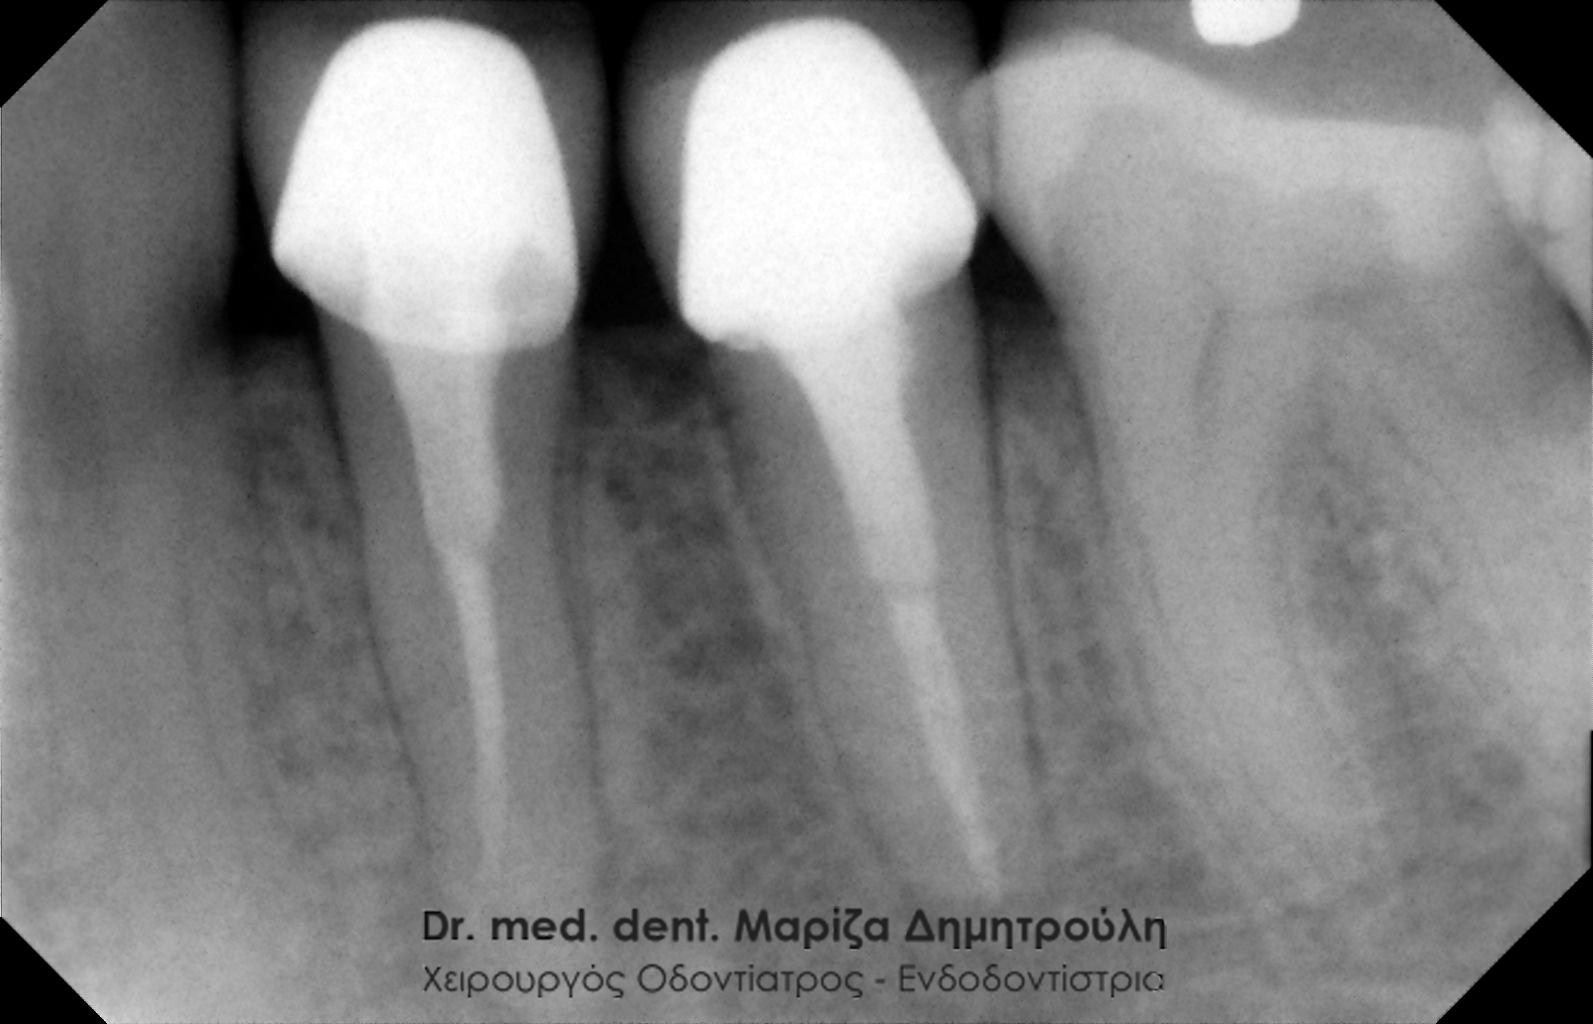

Στο συγκεκριμένο περιστατικό απουσιάζει η αρχική ακτινογραφία. Στην τελική ακτινογραφία φαίνεται η ομοιόμορφη συμπαγής έμφραξη των ριζικών σωλήνων των δοντιών. Επίσης το υλικό απονεύρωσης καλύπτει όλο το μήκος των ριζών του δοντιού, κάτι που είναι σημαντικό για την πρόγνωση του δοντιού.